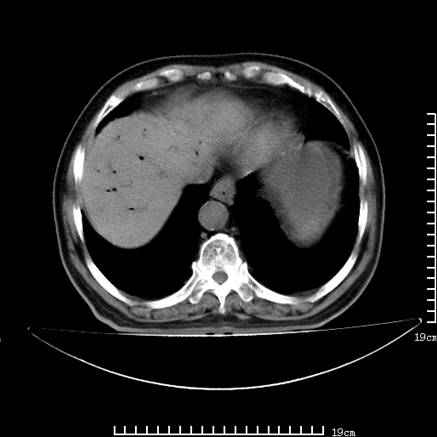

以下是引用zsl6918在2008-7-19 21:53:00的发言:[br]胆总管结石并胆系感染,胆囊切除术后改变。

以下是引用sch2008在2008-7-19 22:03:00的发言:[br]肝内胆管及胆总管积气,并胆总管结石,考虑;胆囊切除术后,胆系感染

以下是引用xinliheng001在2008-7-19 21:59:00的发言:[br]胰头段胆管结石肝内外胆管扩张积气。

以下是引用liaoqiang在2008-7-19 22:26:00的发言:[br]胆总管结石伴胆系感染。